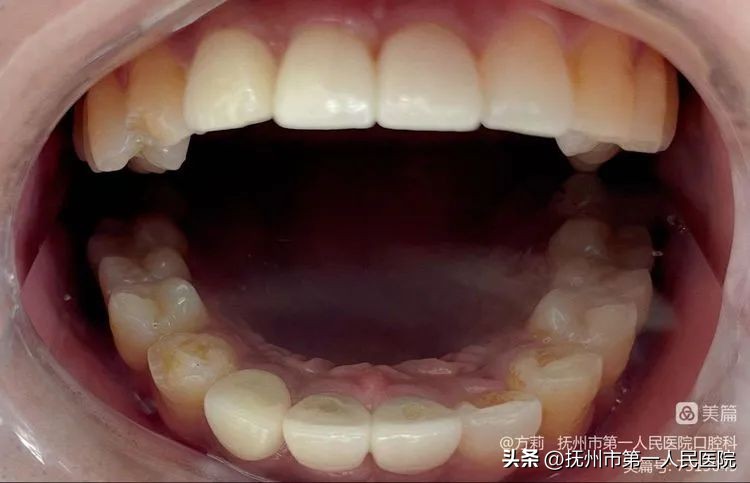

2023年4月,12、11、21永久修复体试戴完成!图为患者口内唇侧观!

患者口内侧面观!

患者口内腭侧照!植体实现了腭侧穿出位,形成良好的穿龈轮廓,且减少了侧向力,利于种植体的长期稳定性!

患者口内切缘观显示:11、21根面突度恢复良好,一定程度上实现了轮廓美学!